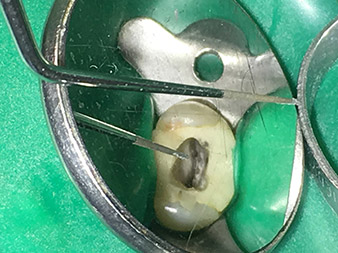

punta 4E

Tratamiento cuidadoso de la base de la cavidad con la punta 4E.

La punta 4E es un instrumento que resulta óptimo para preparar la base de las cavidades en la transición hacia los canales. Aquí es posible redondear a la perfección la transición entre el canal y la base de la cavidad, por lo que surge una tolva en el canal. Además, el instrumento es la opción ideal cuando se trata de eliminar los excesos de dentina de los canales.

En conjunto, con esta punta, la cavidad puede prepararse de forma muy eficaz y mínimamente invasiva, pues permite redondear y alisar de forma óptima los excesos, las esquinas y los bordes.